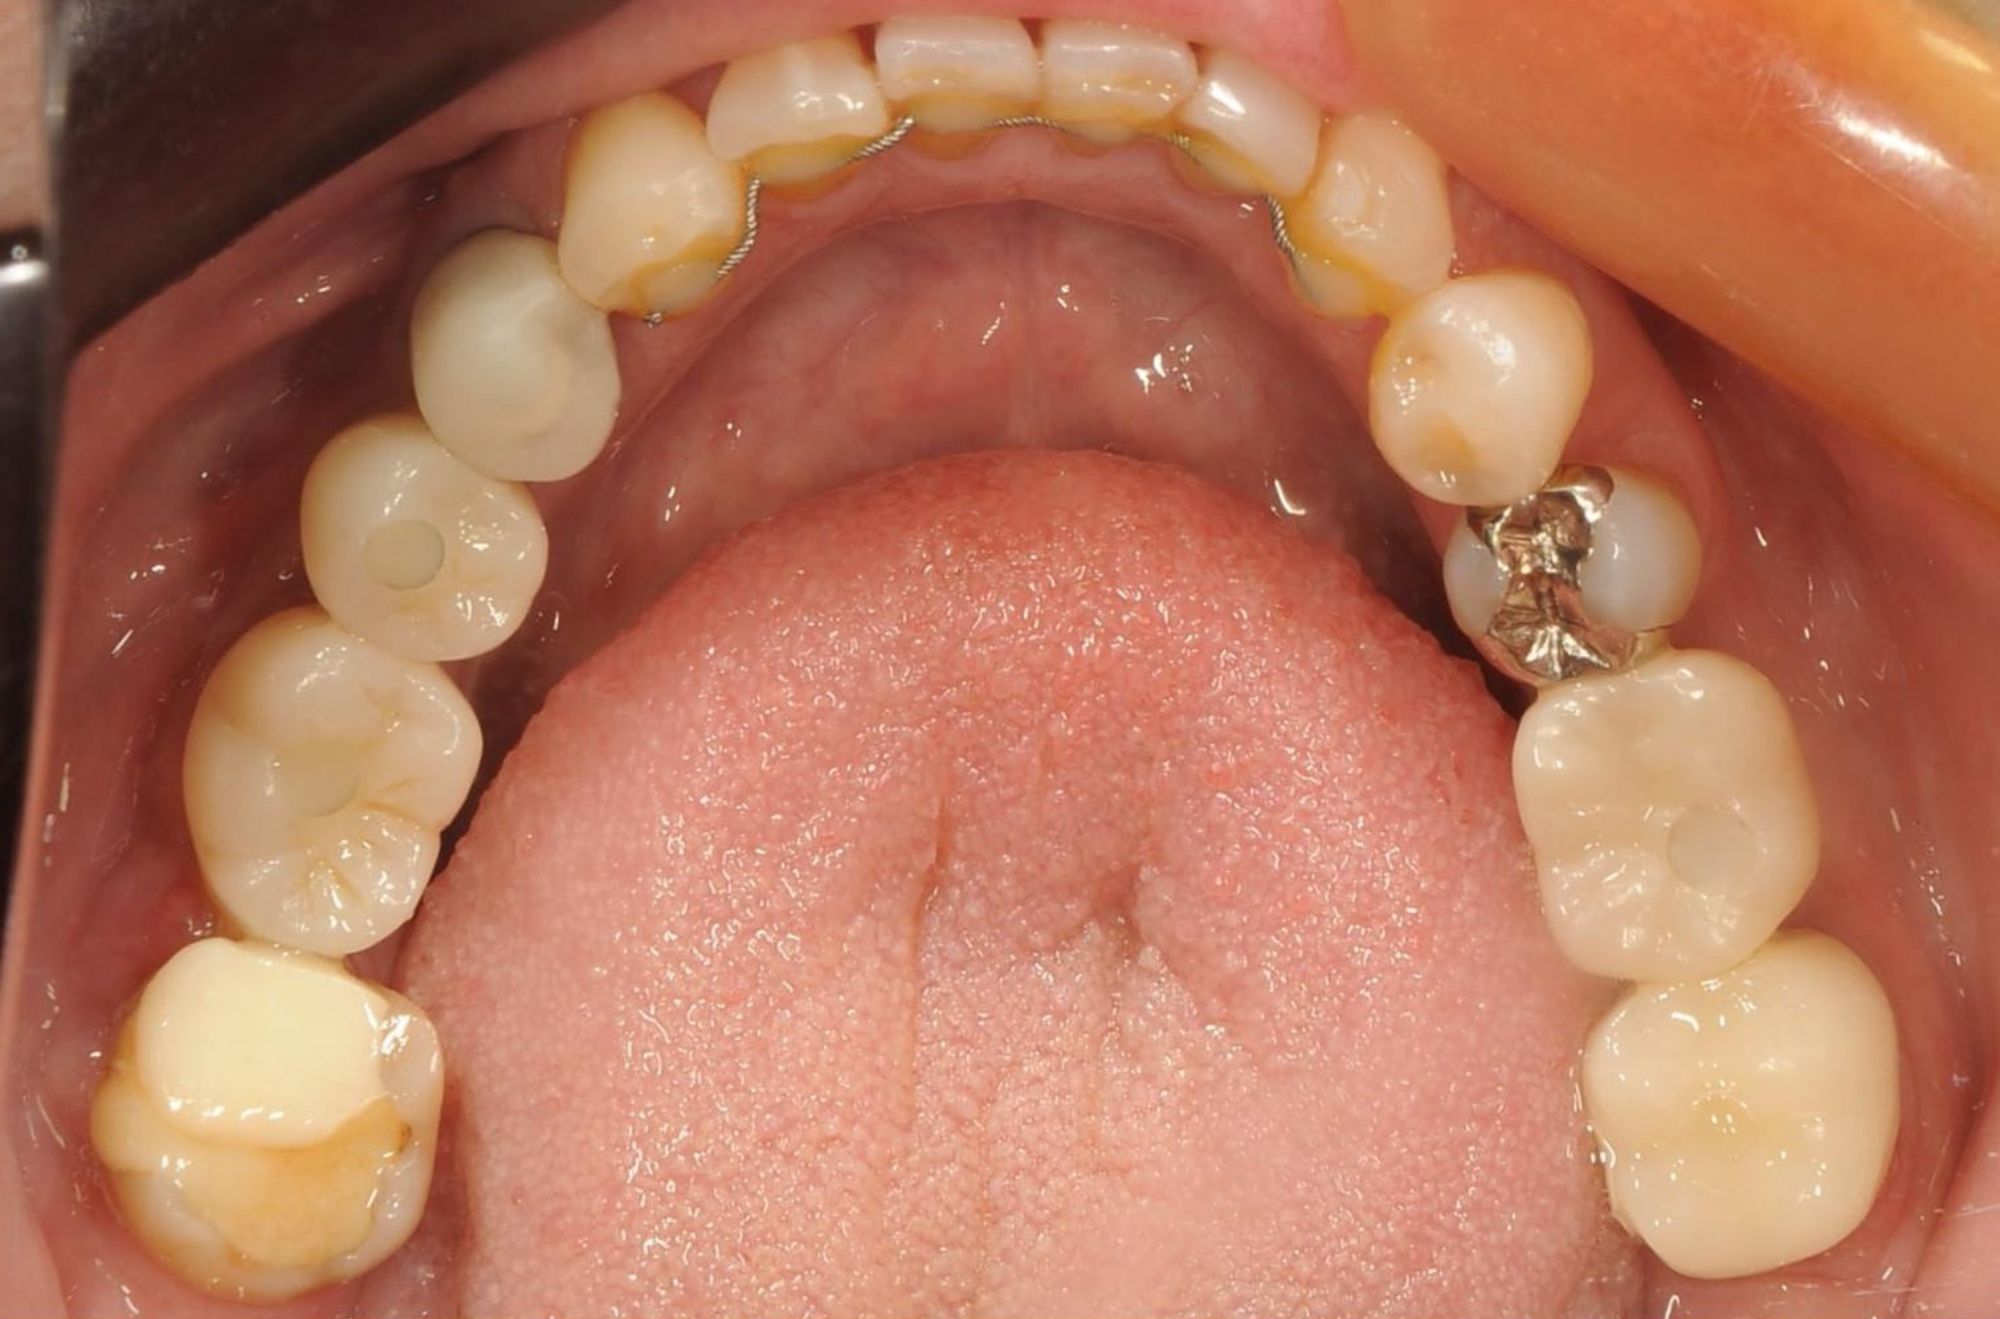

case.01

インプラントで口腔機能の改善

中年の患者様がインプラント治療を希望し来院されました。数本の歯を失っていたため、インプラントを用いて噛む力と審美性を回復しました。治療により、患者様は食事の楽しみを取り戻し、自信を持って笑顔を見せるようになりました。